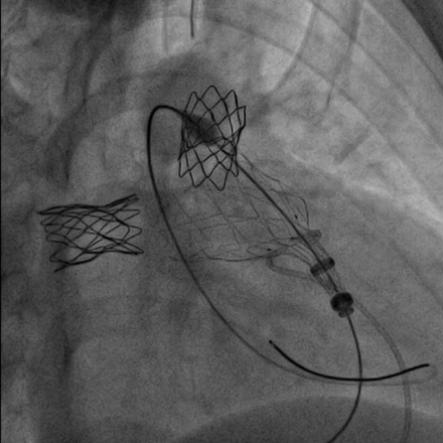

患者在全麻下,首先从左股静脉将造影导管分别送至右心室和肺动脉主干,行造影以明确右室流出道、肺动脉及肺动脉分支的基本情况。同时测量了右室流出道及肺动脉的尺寸。随后输送器通过右侧股静脉延加硬导丝将瓣膜输送到右室流出道,在X线的引导下,将瓣膜精确定位到植入部位并顺利进行瓣膜释放,无反流和瓣周漏,手术效果十分理想。

高主任总结道:本例病例就是在没出现严重肺动脉反流时,先解决了严重的左右肺动脉分支起始部狭窄,不仅促使狭窄远端肺血管的发育,避免了肺动脉分支的闭塞。随着年龄长大,肺动脉反流加剧,右心功能受损时,我们及时植入肺动脉带瓣支架,阻滞了右心功能向失代偿期的发展。

随着介入技术和介入材料的改进,通过经皮介入技术可以替代传统的外科手术。特别是肺动脉支架和肺动脉带瓣支架的应用,替代传统外科手术,可以起到非常好的效果。这2类支架,在同时出现狭窄和肺动脉严重反流时可以同时应用。一次性解决肺动脉分支狭窄和肺动脉反流问题。如果只有肺动脉分支狭窄,反流并不严重时,可以先处理肺动脉分支狭窄,也就是可以在狭窄部位植入Pul-Stent®肺动脉支架进行扩张。一旦解除了狭窄,也会延缓肺动脉反流的加剧。这样可以保护了右心功能,促使肺血管发育,而且会推迟肺动脉反流干预的时间。